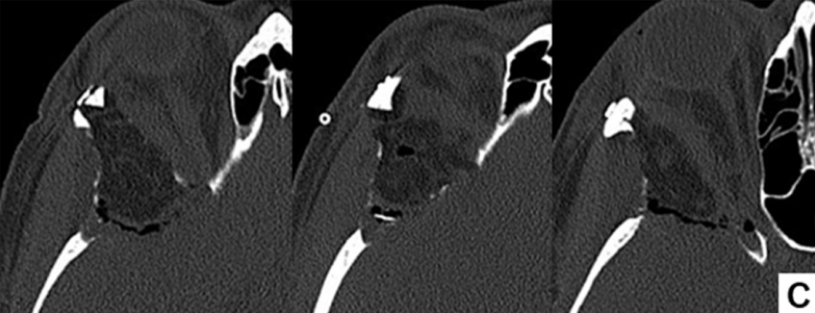

全麻状态下,福洛里希教授主刀实施手术。沿右侧眉毛弧度作月牙形切口,通过显微镜经此切口完成肿瘤切除。术中使用神经内镜进行术腔探查确认无肿瘤残留。取患者腹部脂肪组织填充术区,避免使用人工材料,采用微型钢板和螺钉进行颅骨固定。术后CT证实脑膜瘤及反应性增生骨质完全切除。